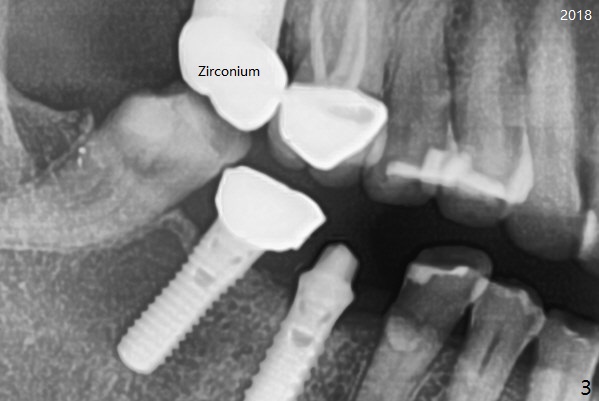

A 50-year-old woman is a bruxer. There are 3 PFM crowns at #3, 30 and 31 (Fig.1). A full metal crown is changed at #31 because of porcelain chip 3 years later (Fig.2). A Zirconium crown is fabricated at #2 after tooth fracture; porcelain chips at #30 and the PFM crown is removed (Fig.3) for Zirconium one (Fig.4). It appears that the weakest link lies between two materials (porcelain and metal of PFM crown) under heavy occlusion and when the implant has no flexible mechanism (periodontal ligament). Either full metal crown or Zirconium one is a suitable crown material for bruxer. Note the dense bone around the implant at #30 (Fig.4 (bruxism)).